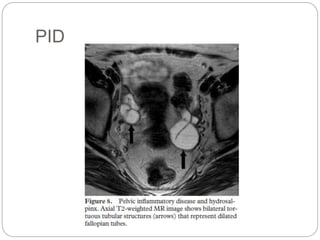

PID